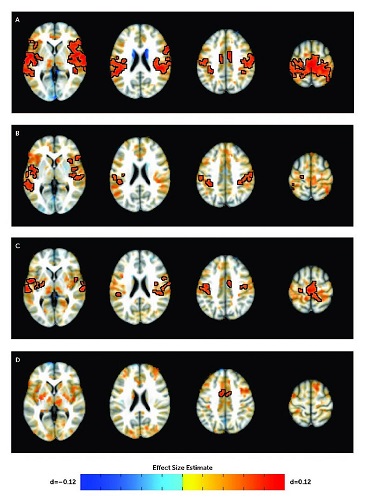

NIH RESEARCHERS IDENTIFY BRAIN CONNECTIONS ASSOCIATED WITH ADHD IN YOUTH

Large study finds atypical interactions between the frontal cortex and information processing centers deep in the brain.

March 13, 2024 – Researchers at the National Institutes of Health (NIH) have discovered that symptoms of attention-deficit/hyperactivity disorder (ADHD) are tied to atypical interactions between the brain’s frontal cortex and information processing centers deep in the brain. The researchers examined more than 10,000 functional brain images of youth with ADHD and published their results in the American Journal of Psychiatry. The study was led by researchers at NIH’s National Institute of Mental Health (NIMH) and National Human Genome Research Institute.

Luke Norman, Ph.D., a staff scientist in the NIMH Office of the Clinical Director, and colleagues analyzed brain images supplied by more than 8,000 youth with and without ADHD sourced from six different functional imaging datasets. Using these images, the researchers examined associations between functional brain connectivity and ADHD symptoms.